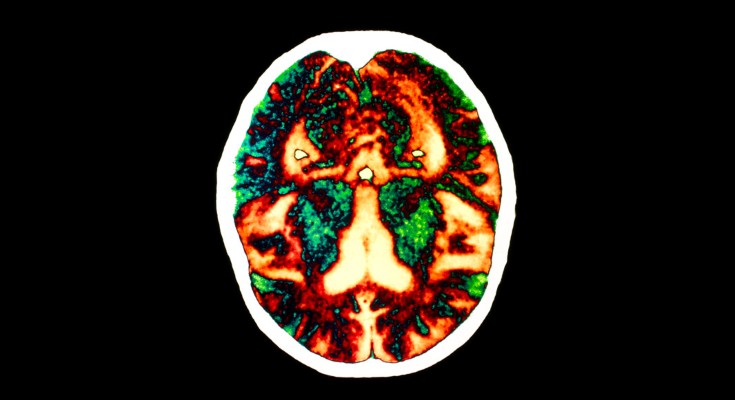

RNA-sequencing analysis of cells in the human cortex enabled identification of diverse cell types, revealing well-conserved architecture and homologous cell types as well as extensive differences when compared with datasets covering the analogous region of the mouse brain.

Whether cell types in the brain have been conserved during evolution is not clear. A comparison of the molecular recipes that define brain cell types in humans and mice reveals similarities and differences between species.

• Matthew G. Keefe

•  & Tomasz J. Nowakowski